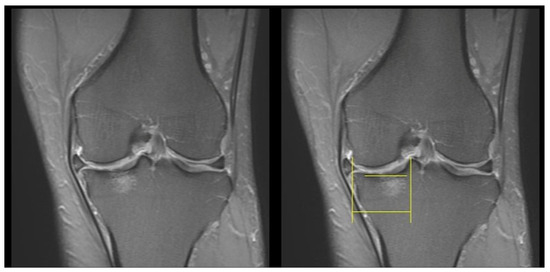

- The length units were calibrated using the 1 cm scale bar in the MRI images;

- An outline was drawn along the subchondral plate horizontally, and the flattened and depressed parts were connected;

- An outline was drawn along the thickened subchondral plate perpendicularly, without ill-defined areas, such that a radiating, disrupted linear pattern was obtained (Figure 2).